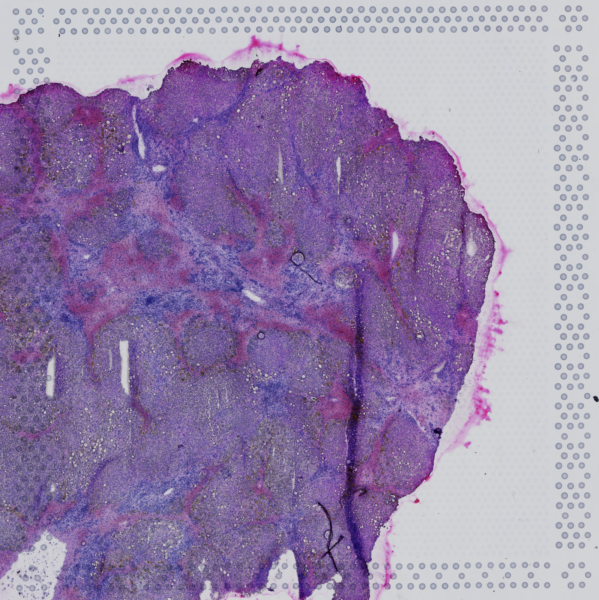

Sample

GSM6963123

Organ

Nonae Liver Explant

Disease

Acute Hepatic Failure

Species

Dataset Statistics

3732

Total Cells

16791

Gene Counts

10131

SNV Counts

Slice

Spatial tissue slice visualization